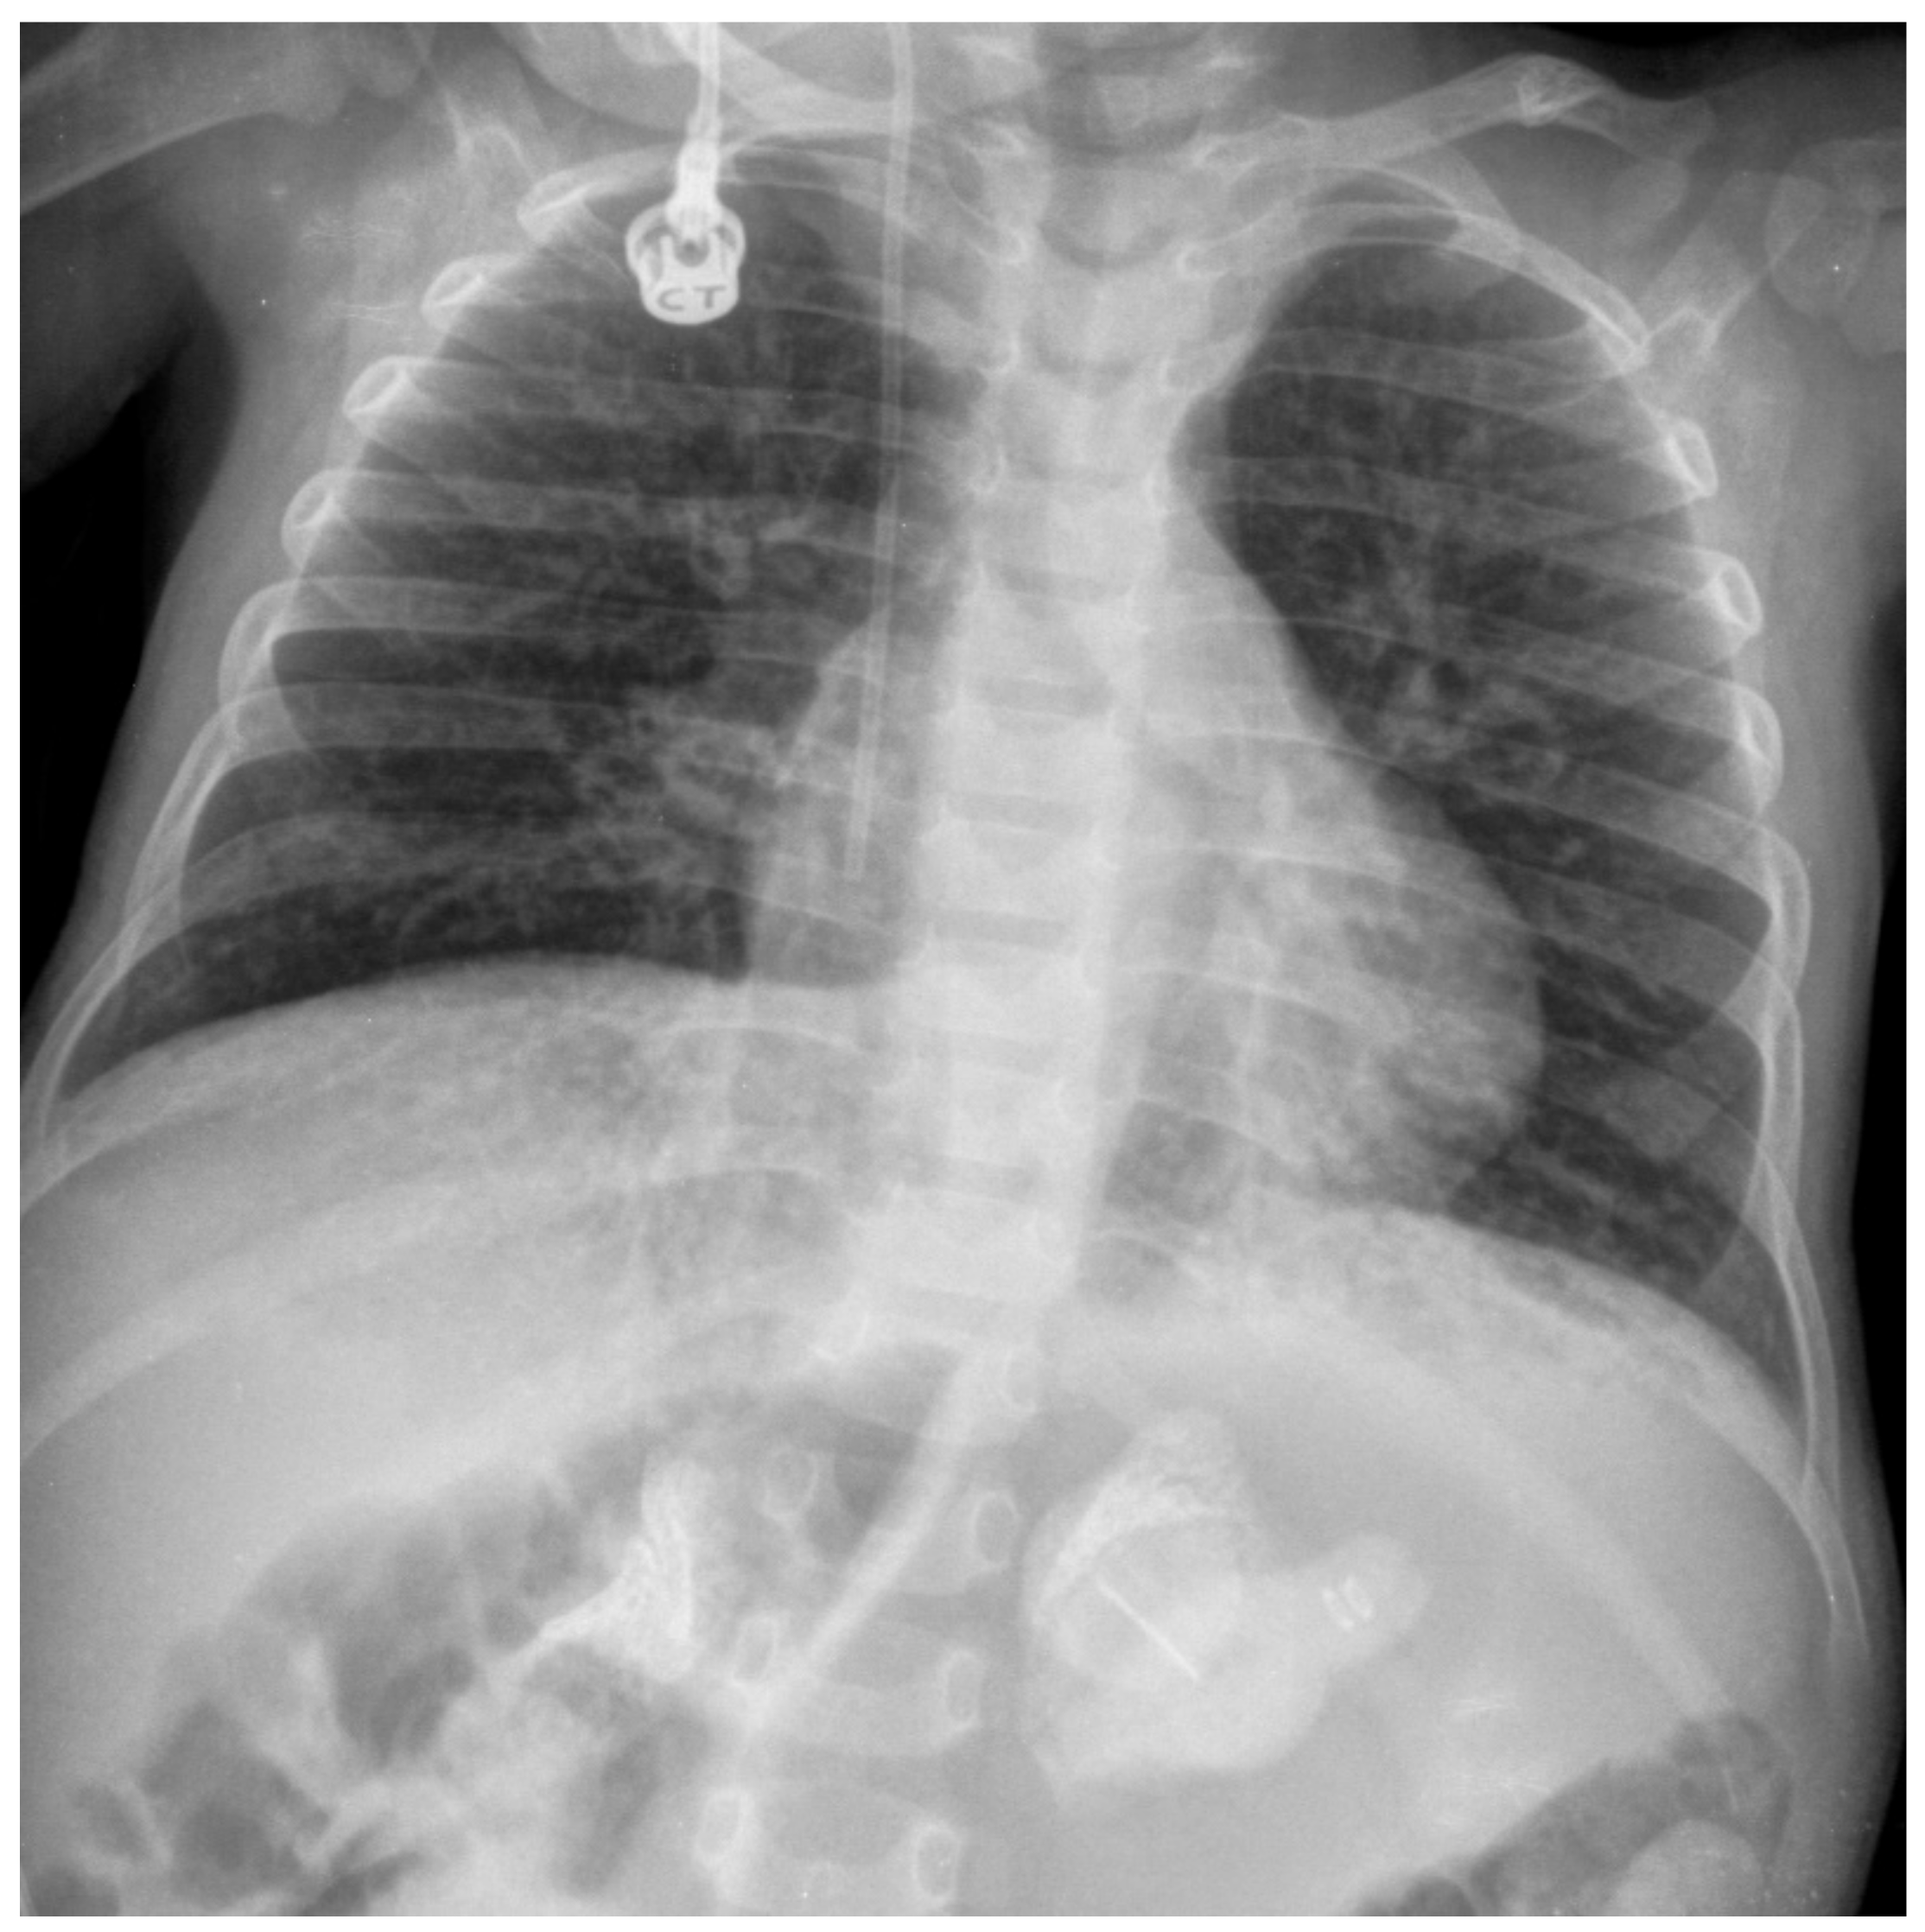

3.1. Infantile-Onset LAL-D (Wolman Disease)